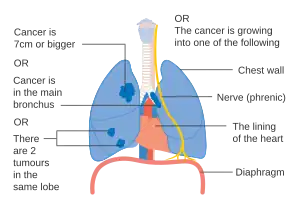

- Diagrams of main features of staging

Stage IIIB lung cancer -